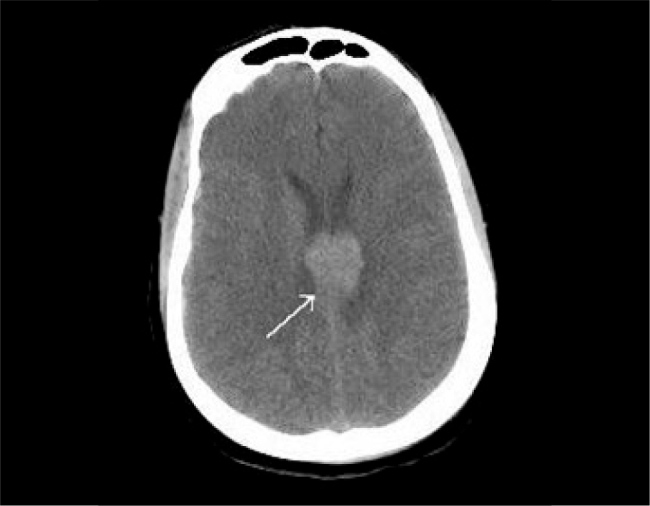

Case report: A 33-year-old woman presented with cervical swelling that had persisted for one month. Ultrasound examination and biopsy confirmed the diagnosis of RDD. The patient subsequently developed raccoon eyes and bilateral eyelid oedema. Laboratory investigations revealed bicytopenia and leukocytosis. Unexpectedly, bone marrow aspirate and flow cytometry confirmed the presence of acute myeloid leukaemia (AML). Following repeated complaints of headache, brain magnetic resonance imaging revealed a callosal lesion, suggestive of a space-occupying lesion. One year later, the patient relapsed and died from septicaemia.